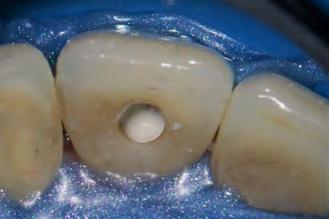

Se inició la terapia endodóntica del diente 21. Después del acceso, el conducto fue irrigado con Hipoclorito de Sodio al 5%, seguido de EDTA al 17%, ambos con PUI y Easy clean. A través del uso del microscopio operatorio, fue posible visualizar la extensión de la cavidad reabsortiva (Figura 5). Durante la preparación químico-mecánica hicimos una irrigación abundante con sustancias químicas auxiliares con capacidad solvente orgánica efectiva y punta de ultrasonido esférica para remover y diluir el tejido pulpar remanente.

En la segunda sesión, 15 días después, realizamos la obturación convencional del tercio apical del canal con gutapercha, llenado de la cavidad reabsortiva con BIO-C ® REPAIR (Angelus, Londrina - Brasil) (Figura 7, 8 y 9), condensándolo contra las paredes con condensadores específicos y bolita de algodón humedecida y realizamos el sellado coronario con resina.

Figura 5 - Cavidad reabsortiva

Figura 7 - BIO-C ® REPAIR (Angelus, Londrina - Brasil).

8 - Radiografia final

9 - Cavidad reabsortiva rellenada com BIO-C® REPAIR